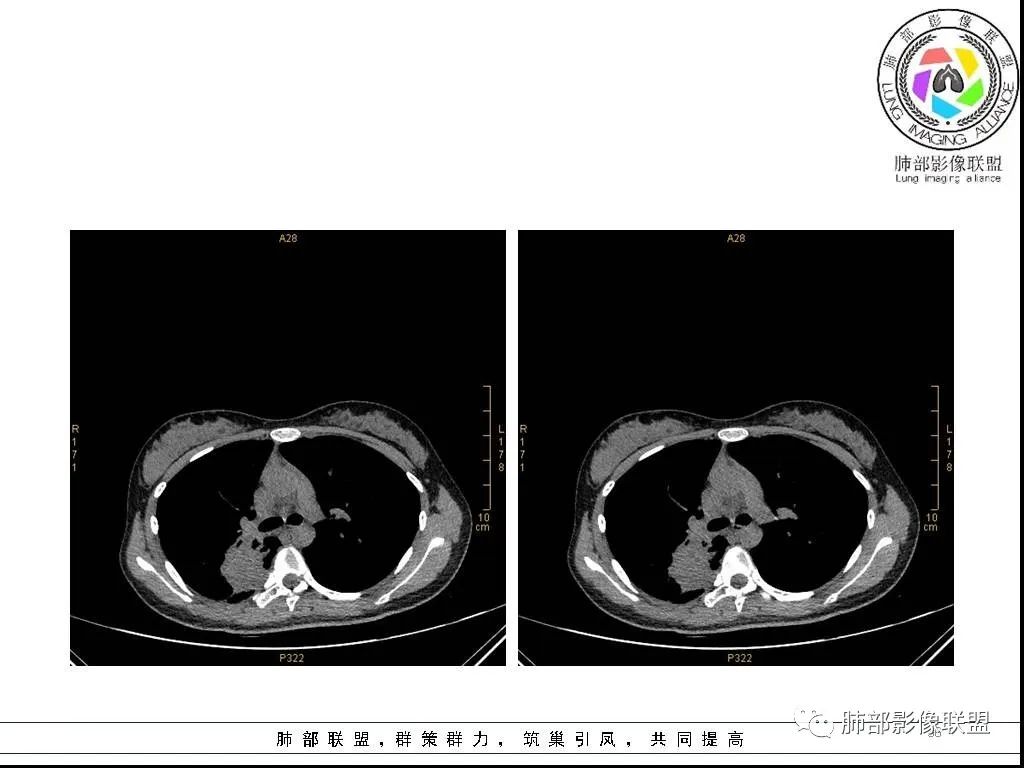

右肺炎症性病变1例CT影像讨论

年轻女性,病程长,咳嗽少痰4个月,辅检未见特殊,CT:右肺团块影,跨叶,主体在下叶背段,外大内小,边缘以膨隆为主,部分平直内收,深分叶,周围有模糊晕,可疑卫星灶,胸膜增厚,糊墙,支气管近端部分进入,粘液栓,有坏死空腔,内壁光整,部分血管侵蚀,强化不均,延迟,明显;同侧R10、7、R4淋巴结肿大,考虑肉芽肿炎,结核,需要与肿瘤鉴别:16岁,女性,诊断肿瘤需要勇气,跨叶多见于炎性,需要进一步活检。

青少年女性,咳嗽咳痰4个月,血沉快,ppd阴性。右肺上叶后段及下叶背段可见一长条块影,边缘平直,有收缩及凹陷,局部有膨隆,长轴与支气管平行,近段支气管似有粘液栓阻塞,血管进入后有破坏,周围有磨玻璃影及少许卫星灶,中度不均匀强化,局部胸膜增厚,少量积液,考虑炎性肉芽肿,肺结核可能性大,鉴别op,淋巴瘤,肺癌。

16岁女性,咳嗽,咳痰4月,无发热,白细胞不高,炎性指标(CRP,PPT)不高,血沉增高(75mm/h)。影像表现:右肺胸膜下不规则肿块影,边缘平直,U型凹陷,桃尖征为主,纵隔窗部分层面似有多个结节融合感,近端支气管扩张,堵塞,局部呈鬼脸样改变。边缘可见长短不一毛刺影,周围见晕征,远端见多个小结节卫星灶。胸膜大面积反应性增厚,增强后不均匀中度渐进性强化,局部干酪样坏死可能(CT值-32~-15)内部血管走行较正常,破坏不明显。 医学百科网 | YxBaike.Com

这个病例的特点:病灶贴近斜裂内侧区域,范围较大,直达肺门区。右肺上叶,前、尖、后段前移,病灶嵌塞于上叶后段支气管的后下方区域,未能跟踪到病灶与叶段支气管关系。应当怀疑有额外的支气管存在,也就是副叶。因为这么大的病灶,这么粗大肺动脉进入,伴行的支气管应当比较粗大,但是没能观察到较大的支气管与其相延续。

病灶明显是由靠近斜裂这个方向朝肺门侧蔓延的,外围大,内带小,病灶远端没有阻塞的肺组织,伴行的肺动脉是包绕之中的。这不符合肺门区的支气管黏液栓堵塞或肺门区的大肿块(堵塞支气管),它的病灶变化不是这样的。

病灶收缩、跨叶,应当想到存在有畸形的、发育异常的叶裂,一个副叶的病变。这个病灶明显在后段下方,斜裂的上方,靠近肺门侧的叶裂显示不是很清楚,这个应该是副叶来的,不是后段的分支。

病灶内部存在管状分布液性低密度区,这与复查显示的柱状管样气腔对应吻合,支持先天性支气管扩张的存在,仅仅是影像未能显示出入口。